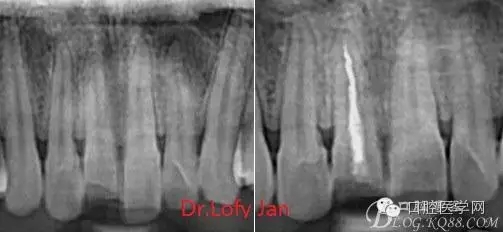

《數(shù)字化根尖片、曲面斷層片、CBCT測量牙齒長度準(zhǔn)確性的比較研究》文中顯示:平行投照數(shù)字化根尖片影像長度和牙齒實(shí)際長度之間無顯著性差異(P0.05);數(shù)字化曲面斷層片影像長度和牙齒實(shí)際長度之間有顯著性差異(P0.05),平均失真率為17.05%。CBCT冠狀面測量結(jié)果中除上頜前磨牙區(qū)、下頜前磨牙區(qū)與真實(shí)長度差異無統(tǒng)計(jì)學(xué)意義(P0.05)外,其余6個(gè)分區(qū)差異均有統(tǒng)計(jì)學(xué)意義(P0.05);矢狀面測量結(jié)果中上頜磨牙區(qū)、下頜磨牙區(qū)、下頜前磨牙區(qū)、下頜尖牙區(qū)、下頜前牙區(qū)與真實(shí)長度比較差異均有統(tǒng)計(jì)學(xué)意義(P0.05)。結(jié)論平行投照數(shù)字化根尖片較曲面斷層片和CBCT能更加精確地反映牙齒的真實(shí)長度。

病例分析:曲面斷層片在x線輔助診斷與檢查中目前大多數(shù)文獻(xiàn)和著作都建議只能作為初診拍片檢查手段,不能作為終末疾病的確診與手術(shù)療效的評價(jià)指標(biāo),臨床大部分中小型門診都因?yàn)樵O(shè)備不齊全導(dǎo)致信息偏差很大。